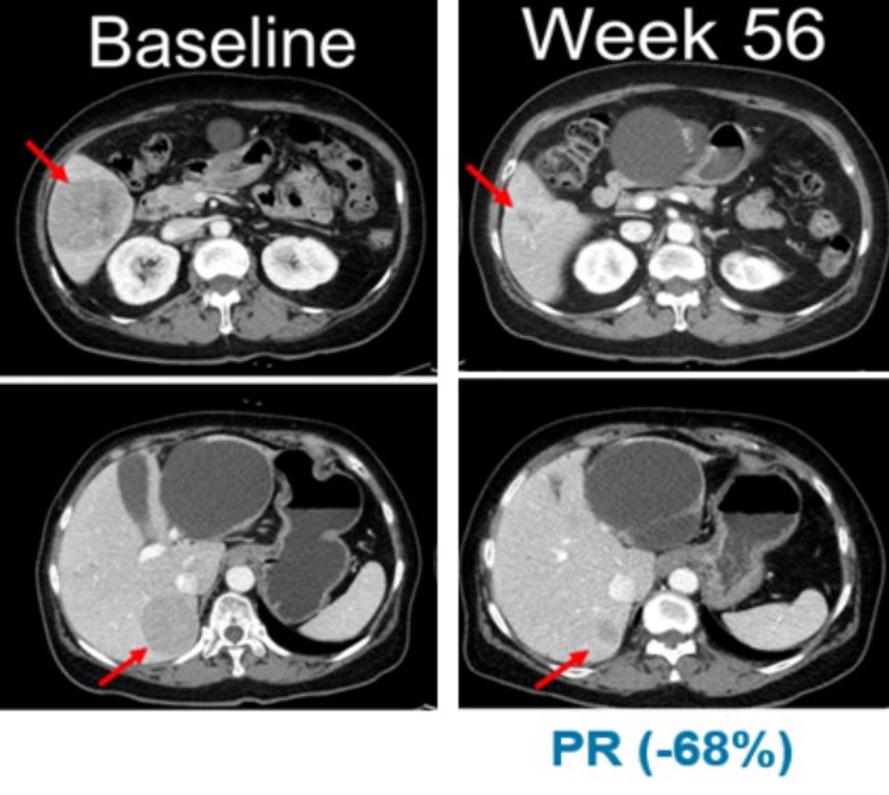

사진 = 벨바라페닙 투여 후 흑색종 변화(한미약품 제공).

한미의 또다른 파트너사 제넨텍은 진행성 고형암환자를 대상으로 벨바라페닙과 코비메티닙 병용요법을 진행한 연구결과를 구연으로 발표했다.

적응증 확장 임상의 NRAS 변이 흑색종 연구에서는 13명의 환자 중 5명이 부분반응(PR)을 보였으며, 최고반응률(BORR)은 38.5%로 나타났다.

13명의 환자 중 11명은 이전에 면역관문억제제(CPI)를 투여 받았으며, 면역관문억제제 투여 환자군 대상 최고반응률(BORR)은 45.5%로 확인됐다. 무진행생존기간(PFS)의 중간값은 7.3개월이다.

발표를 진행한 신상준 교수는 "연구를 통해 벨바라페닙의 우수한 안전성 및 항암효과를 확인했다"며 "특히 NRAS 유전자 돌연변이를 지닌 흑색종 환자에서 고무적인 효과를 확인할 수 있었다"고 말했다.